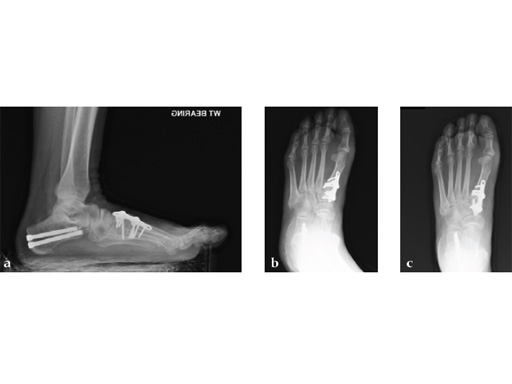

Case 2: First MTP fusion plate

A 38-year-old man presented for opinion after two attempts to fuse the big toe MTP joint. The AP view is significant for luscency at the joint line. The lateral view is notable for loosening of the hardware and malposition because of the dorsiflexion built in to the precontoured implant. Revision was planned using a 0 variable angle locking/compression hallux MTP plate.

At 10 weeks postoperatively (see Fig. 2ab) the patient had no pain with weight bearing. The lateral view demonstrates improved position of the toe using a 0angle plate.